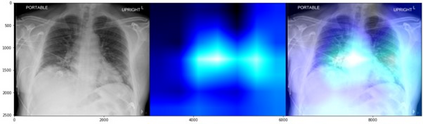

Deep learning (DL) analysis of Chest X-ray (CXR) and Computed tomography (CT) images has garnered a lot of attention in recent times due to the COVID-19 pandemic. Convolutional Neural Networks (CNNs) are well suited for the image analysis tasks when trained on humongous amounts of data. Applications developed for medical image analysis require high sensitivity and precision compared to any other fields. Most of the tools proposed for detection of COVID-19 claims to have high sensitivity and recalls but have failed to generalize and perform when tested on unseen datasets. This encouraged us to develop a CNN model, analyze and understand the performance of it by visualizing the predictions of the model using class activation maps generated using (Gradient-weighted Class Activation Mapping) Grad-CAM technique. This study provides a detailed discussion of the success and failure of the proposed model at an image level. Performance of the model is compared with state-of-the-art DL models and shown to be comparable. The data and code used are available at https://github.com/aleesuss/c19.